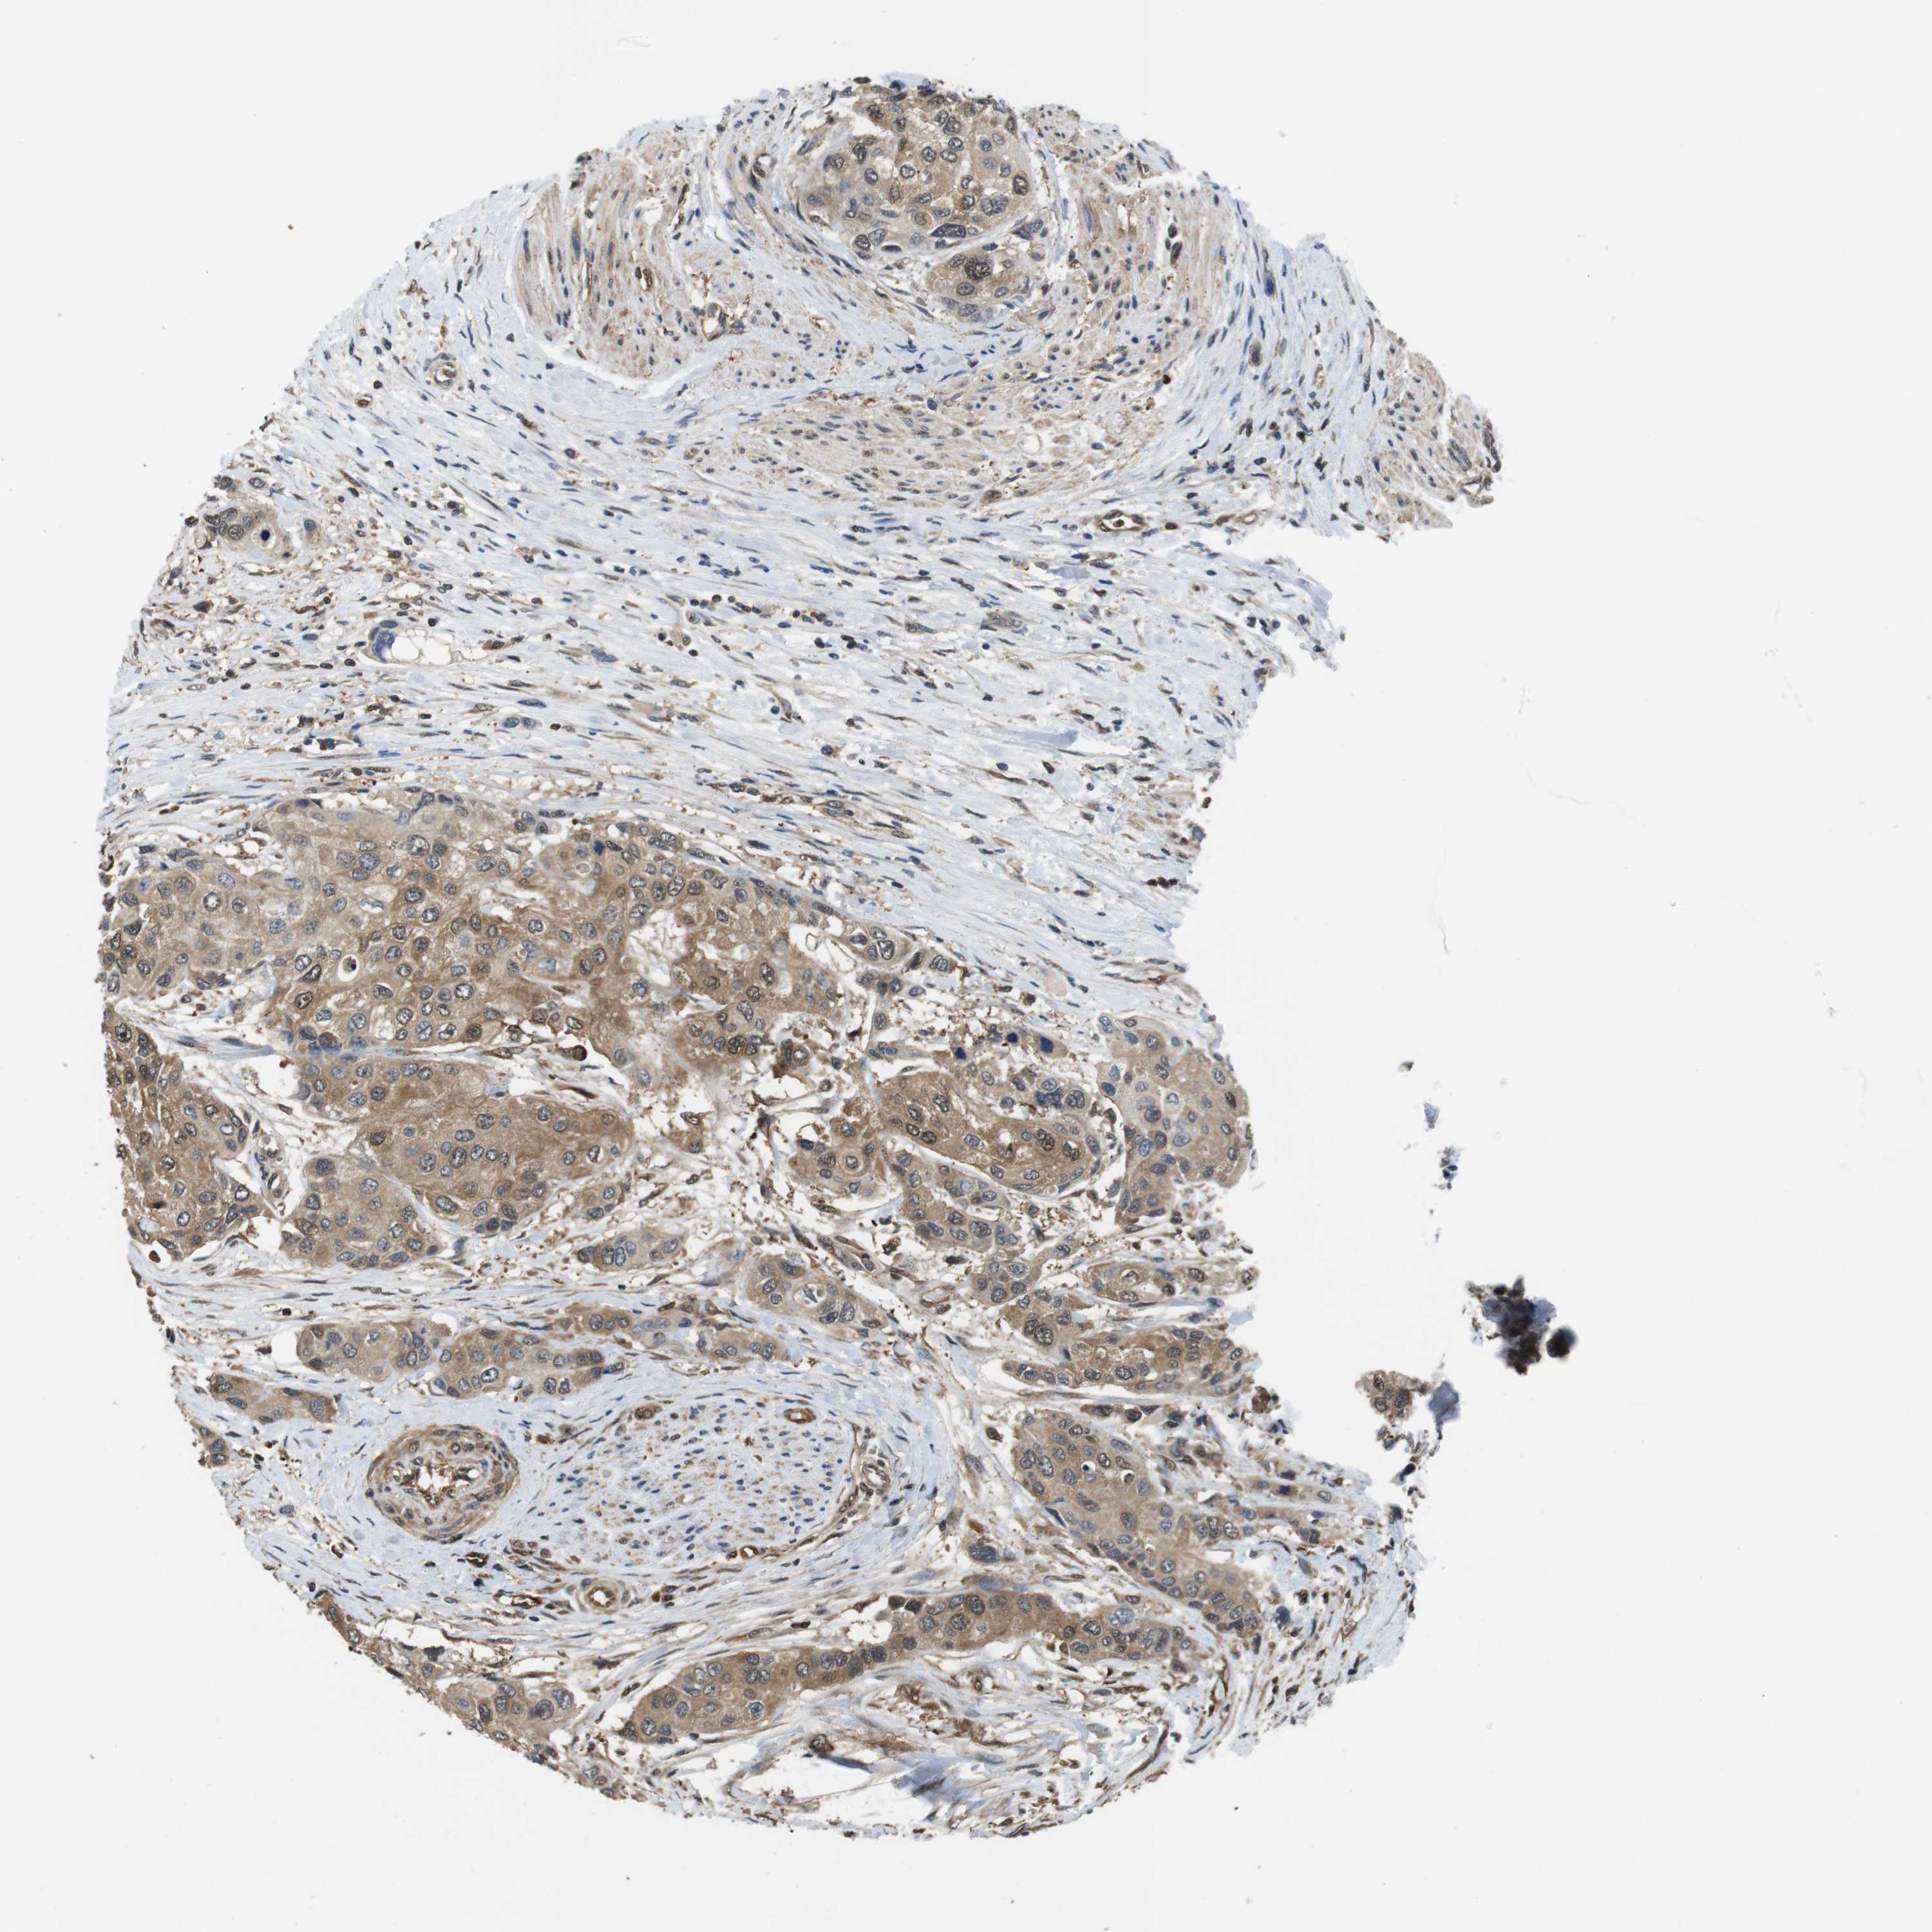

UROTHELIAL CANCER - Protein expressioni

A mouse-over function shows sample information and annotation data. Click on an image to view it in a full screen mode. Samples can be filtered based on level of antibody staining by selecting one or several of the following categories: high, medium, low and not detected. The assay and annotation is described here.

Note that samples used for immunohistochemistry by the Human Protein Atlas do not correspond to samples in the TCGA dataset.

Antibody stainingi

Antibody staining in the annotated cell types in the current human tissue is reported as not detected, low, medium, or high, based on conventional immunohistochemistry profiling in selected tissues. This score is based on the combination of the staining intensity and fraction of stained cells.

Each image is clickable and will lead to virtual microscopy that enables deeper exploration of all samples and also displays staining intensity scores, fraction scores and subcellular localization as well as patient and tissue information for each sample.

Antibody CAB015336

Antibody CAB069404

Staining

High

Medium

Low

Not detected

Intensity

Strong

Moderate

Weak

Negative

Quantity

>75%

75%-25%

<25%

None

Location

Nuclear

Cytoplasmic/membranous

Cytoplasmic/membranous,nuclear

Urothelial carcinoma, Low grade

Urothelial carcinoma, High grade

Urothelial carcinoma, NOS